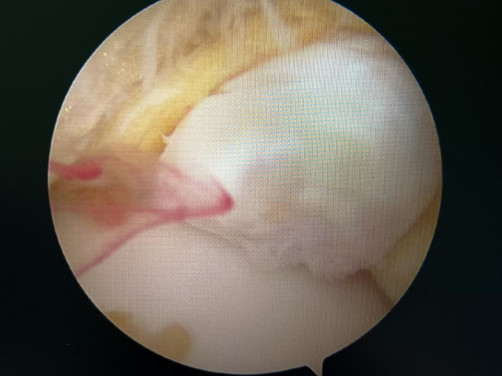

前方長(zhǎng)骨刺

踝關(guān)節(jié)鏡見(jiàn)前方長(zhǎng)骨刺

醫(yī)生們?cè)谑中g(shù)中發(fā)現(xiàn),李先生的右踝關(guān)節(jié)軟骨損傷明顯,踝關(guān)節(jié)前方及內(nèi)外側(cè)均有不同程度的骨質(zhì)增生,相互撞擊引起疼痛,同時(shí)距腓前及跟腓韌帶斷裂。手術(shù)醫(yī)生利用磨鉆,小心翼翼將引起撞擊的骨刺一一去除,然后,修復(fù)了損傷的關(guān)節(jié)軟骨,最后,為他完成了距腓前和跟腓韌帶的修復(fù)。